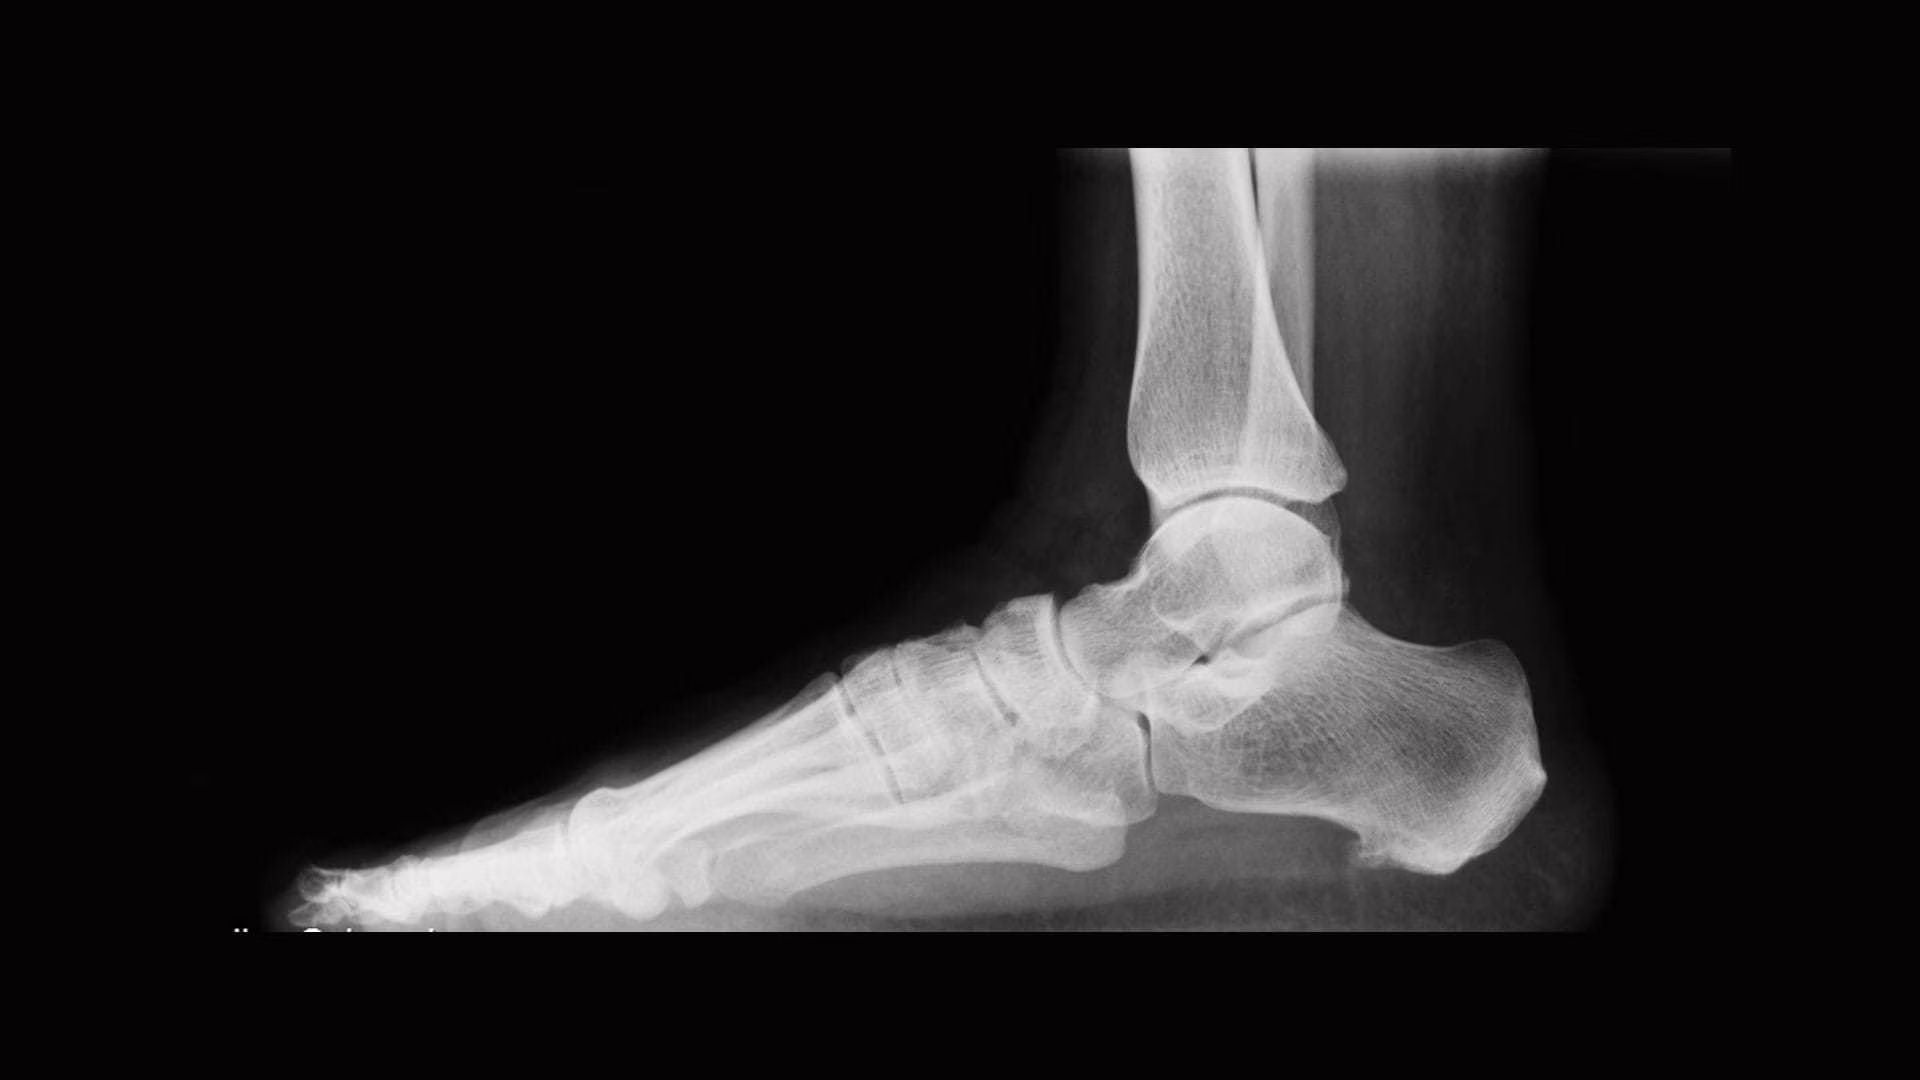

Alle pazienti che si presentavano in studio chiedeva di spogliarsi completamente. Anche se, in realtà, doveva eseguire delle semplicissime radiografie in parti di corpo come le caviglie. Ma adesso il tecnico radiologo finisce nei guai. L’uomo, che lavora a Gallarate, nella provincia di Varese, è stato infatti denunciato per violenza sessuale, aggravata dalla qualifica di pubblico servizio.

Per effettuare una radiografia alla caviglia, infatti, il tecnico le avrebbe chiesto di togliersi i pantaloni e rimanere con la biancheria intima. Ma, poco dopo, le avrebbe anche sfilato anche quella, lasciandola praticamente nuda. La “scusa” era quella di dovere “estendere il controllo anche al femore“.

“Solo al ritiro degli esiti radiografici la donna scopriva in realtà essere stata oggetto di attenzioni sessuali, rilevando che l’esame strumentale fosse stato effettuato esclusivamente alla caviglia e non anche al femore come invece indicato dal tecnico”, sono state le informazioni poi diffuse dalla polizia.